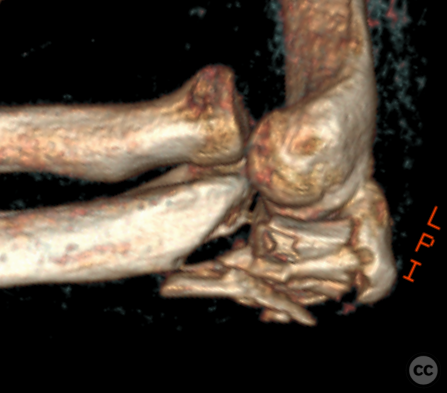

Anteromedial Facet and Sublime Tubercle...

Schleswig Holstein, Germany

Ulna - AO/OTA 2Ux

O'Driscoll type II coronoid fracture dis...

Endobutton fixation of an O’Driscoll ant...

Brussels, Belgium